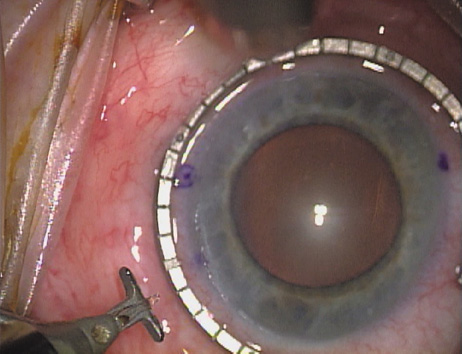

Case 2 is a 79-year-old woman who presented with a very dense left cataract. Her refraction was recorded at −2.25 +2.75 × 125 with a difficult end point. Her manual keratometry and topography measurements were consistent and revealed slightly less than 1.75 D at 120 degrees. Because of the questionable refraction, greater value was placed on the corneal measurements. Based upon the cataract nomogram, the plan was for paired LRIs of 40 degrees to be placed over the steep 120-degree axis (Figs. 1219).

Fig. 12. In this left eye, the steep meridian is at the 120-degree axis and has been delineated by opposing limbal marks. The upper left hand ink mark represents the 6:00 position for orientation. (Reprinted from Hardten DR, Lindstrom RL, Davis EA. Phakic Intraocular Lenses: Principles and Practice. Thorofare, NJ: SLACK Incorporated, 2004, with permission.)

Fig. 13. The incision is begun 20-degrees to one side of the centering mark. (Reprinted from Hardten DR, Lindstrom RL, Davis EA. Phakic Intraocular Lenses: Principles and Practice. Thorofare, NJ: SLACK Incorporated, 2004, with permission.)

Fig. 14. The incision is completed. (Reprinted from Hardten DR, Lindstrom RL, Davis EA. Phakic Intraocular Lenses: Principles and Practice. Thorofare, NJ: SLACK Incorporated, 2004, with permission.)

Fig. 15. Total arc length equals 40 degrees. (Reprinted from Hardten DR, Lindstrom RL, Davis EA. Phakic Intraocular Lenses: Principles and Practice. Thorofare, NJ: SLACK Incorporated, 2004, with permission.)